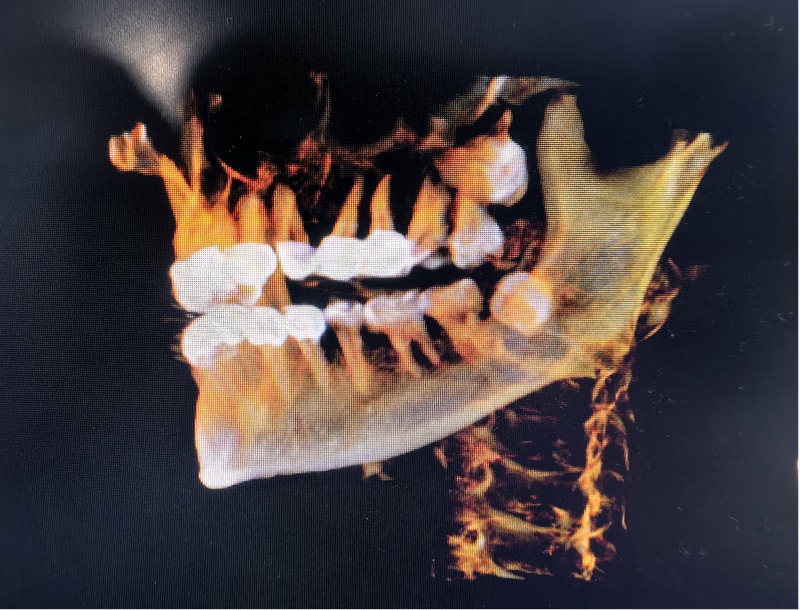

術前:尖牙橫行貫穿埋伏于左上頜骨內,牙冠位于上腭,牙根位于鼻根側下方。

劉弦醫生仔細查看口腔錐形束CT影像,發現這顆左上頜埋伏尖牙堪稱“定時炸彈”——碩大的牙根死死壓迫鄰牙,稍有拖延便會連累鄰牙不保。更棘手的是,這顆牙前臨鼻腔、后靠上頜竇,周圍纏繞著鼻腭神經血管束,拔除時稍有偏差,牙體就可能墜入鼻腔或上頜竇;面對謝女士“希望門診局麻下拔牙”的請求,這個手術難度堪比在精密儀器上“穿針引線”。